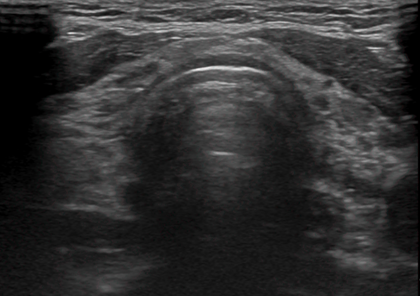

3) 갑상선 초음파

갑상선 조직의 변화나 염증 여부를 확인합니다. 갑상선 기능 저하증이 있는 경우 초음파로 보이는 갑상선의 모습이 다른 사람들보다 거칠어 보일 수 있습니다. 이러한 상태는 갑상선 결절을 구분하기 어렵기 때문에 일반인들보다 더 자주 초음파를 해보는 것이 좋습니다.